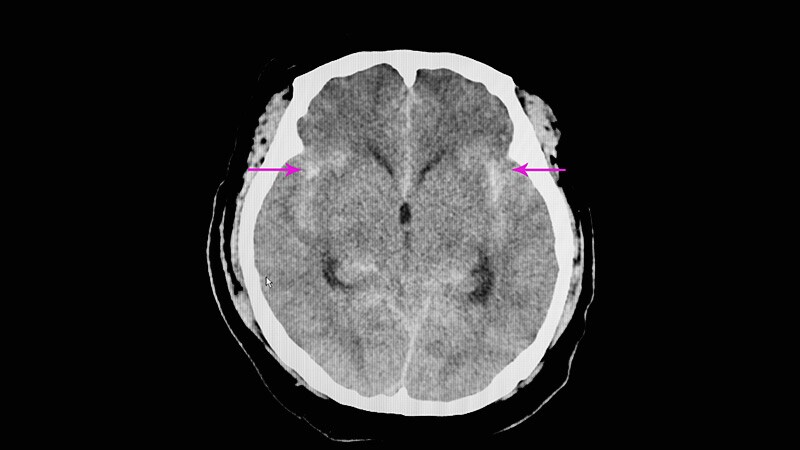

Ticagrelor Better Prevents Stroke in Poor Clopidogrel MetabolizersIn stroke patients carrying CYP2C19 loss-of-function alleles that impede metabolism of clopidogrel, ticagrelor was more effective

than clopidogrel at reducing recurrent stroke in the CHANCE-2 trial.